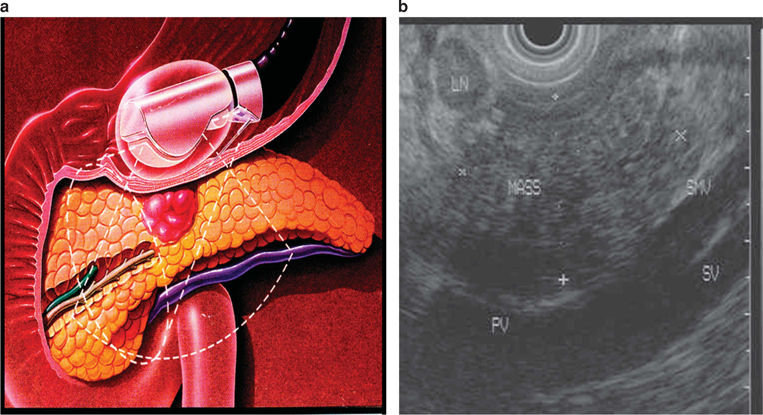

Если диагноз подтверждается, активно ищем опухоль в поджулудочной железе (она может быть очень маленькой и недоступной не только для стандартного УЗИ, но и для МРТ и КТ). Лучше всего ее видно на эндо-УЗИ: при этом сложном исследовании датчик УЗИ заводят в кишечник, чтобы посмотреть поджелудочную поближе, так сказать, с "другой стороны":